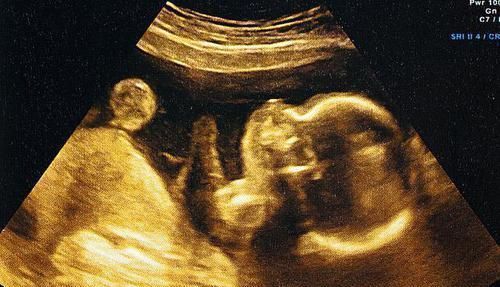

别看现在B超使用率很高,感觉技术相当成熟的样子,其实行内人都知道,它的问题极多,比如最关键的一条:成像模糊。

B超的工作原理是声波与光波技术结合而成,通过特殊的算法,将这些检测手段反馈的数据进行分析,最后形成图形供给医生诊断。